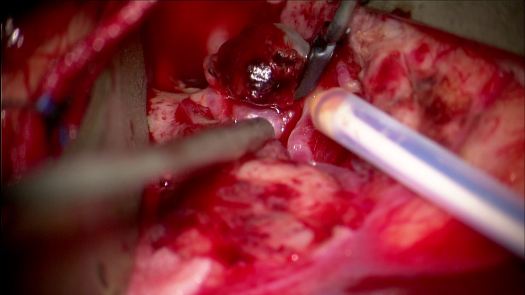

Clipping di aneurisma complesso M1-M2 di sinistra – ricostruzione biforcazione arteria cerebrale media